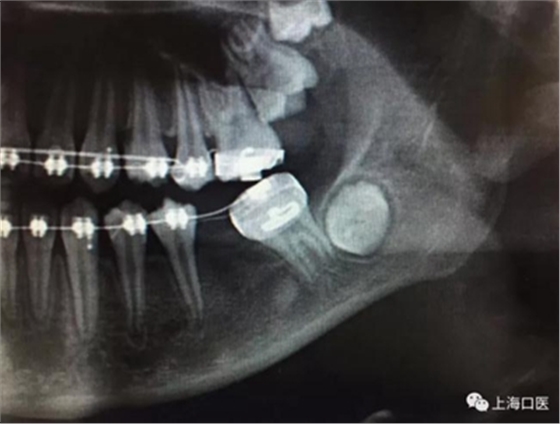

這是上海武廣增正畸工作室接診的一例非常規(guī)拔牙矯治病例,患者女性,初診年齡14歲。LL6殘冠拔除。LL7近中平移取代LL6,我們上傳了該患者一組下頜磨牙近中平移連續(xù)矯治過程的正畸X線片,與正畸界朋友分享。